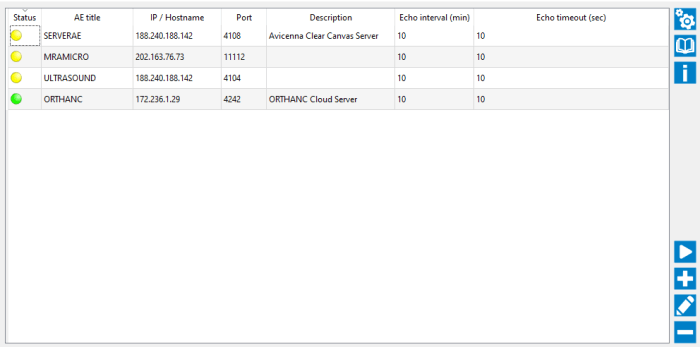

The DICOM PACS Server is a medical imaging software designed to store, retrieve, and distribute medical images and associated data in compliance with the DICOM standard.

Our PACS Server provides a lightweight, open-source solution with features such as DICOM networking, anonymization, query/retrieve capabilities, and support for various medical imaging modalities like X-ray, MRI, CT scans, etc. It's highly customizable, scalable, and can be integrated with other healthcare IT systems, making it a popular choice for managing medical image archives.

DICOM PACS Servers/Clients Solutions are must for Big Hospitals or Radiology Diagnostic Imaging Centers. We are building Cloud based Radiology Diagnostic Imaging Centers.

Multi Modalities

Supports All Modalities

X-Ray, CT, MR, ULS, RF, PET, Dental, Fundus, OCT

Integration

- DICOM Viewer.

- Vol Rendering Plugin.

- Worklist Plugin.